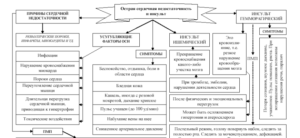

Из этой статьи вы узнаете, что такое легкая форма коронавируса, каковы первые симптомы, как долго он длится, можно ли лечить в домашних условиях и какие лекарства используются. Что значит легкая форма коронавирусной инфекции Любое течение инфекции без пневмонии официально признано легкой формой коронавируса. На практике существует 4 формы Sars-Cov-2: латентная — без симптомов; мягкий — …